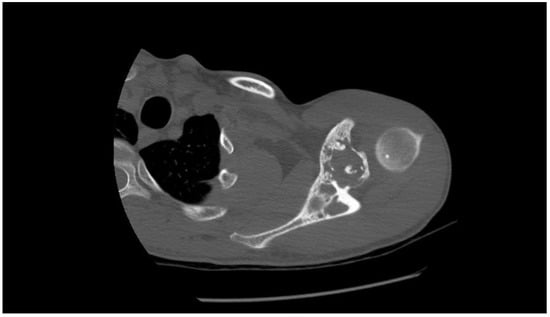

2.1. Oncological Staging